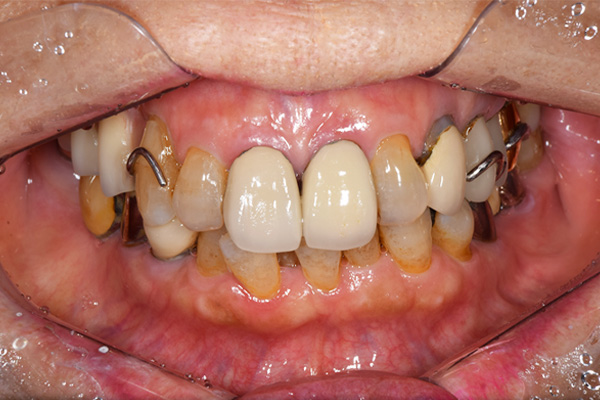

ケース1(自費の部分入れ歯)

前歯が折れて当院にいらっしゃいました。 過去に下の入れ歯を作ったが、合わなくなってずっと入れ歯をいれていらっしゃらない患者様でした。 これは奥歯で噛むことができないため、前歯で噛むことを繰り返したために、負担に耐えられなくなった前歯が折れてかぶせ物ごと 外れてしまったのだと考えられます。 痛くない、違和感の少ない、下の入れ歯を作ることがこの方のゴールであると考えられました。

金属を使用して、薄く違和感が少ない入れ歯が完成しました。 また、見た目にも気を使い、バネが見えにくい様な構造にしました。

入れ歯をお口の中にいれた状態です。前歯もMTMといって、歯を少し引っ張り出す処置を行なったことで、しっかり残せて、またかぶせ物をしました。

年齢 70歳・女性

主訴 前歯が取れた

治療期間 8ヶ月

治療費 .MTM:110,000円

.ファイバーコア:16,500円

.E-maxクラウン:110,000円

.義歯:660,000円

治療方針 長年使ってきた義歯の人工歯が磨耗し、臼歯部での咬合がすくなくなり、前歯部での接触が強くなったことで生じた前歯の破折なので、義歯も作り変える必要がある。

治療内容 前歯部MTMと同時に審美面の回復。

MTM中に義歯の作成も同時に行う。

最終的に義歯と前歯のクラウンを同時にいれる。

義歯は下顎で、しっかり噛めること、違和感の少ないものという希望があったため、なるべく入れ歯を薄く作成するために金属をしようした義歯とした。

また、見た目もあまり義歯が目立たない様に、バネの部分を見えにくいように作成した。

特記事項 歯にもともと入っていた金属の種類によっては、歯自体の変色を治療で変えられないこともある。 義歯は作ってから痛みがでることがありますが、それは調整を行うことで痛くなくすることができます。